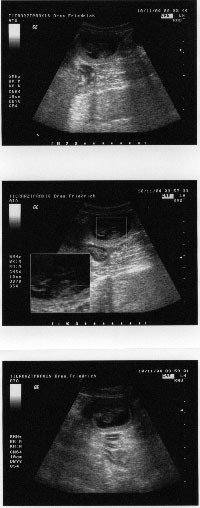

10.11.2004: Welch eine Freude!!!

30.11.2004: Am 50. Tag ist es nicht mehr zu übersehen - in knapp 2 Wochen ist es schon soweit...